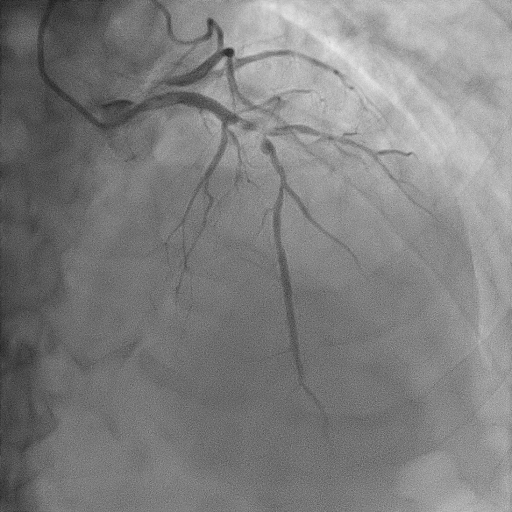

Relevant Catheterization Findings

The coronary angiography revealed normal and short left main coronary artery. The proximal to mid left anterior descending artery had severe stenosis of 90% with thrombus. The proximal segment of diagonal 1 had 80% stenosis. The proximal and distal left circumflex artery showed 50% and 80% stenosis respectively. The right coronary artery showed mild lesion of 20-30% at mid segment. The posterior left ventricular artery showed moderate stenosis of 50% at mid segment.

We proceeded with delayed selective PCI to the left anterior descending artery (LAD). The left main coronary artery (LMCA) was engaged with guiding catheter Medtronic Launcher 6FR EBU 3.5. The PTCA guide wire Shun R (SHUNMEI Medical) crossed the lesion with ease. Besides, we wired the diagonal 1 with PT2 (Boston Scientific) to provide side branch protection. The proximal to mid segment of the LAD lesion was pre-dilated with Sapphire NC 24 PTCA balloon 3.0x15mm and inflated to 12 atm. The lesion was stented with Xience Xpedition 3.0x48mm and inflated to 10atm. The stent was post-dilated with NC Trek balloon 3.5x12mm and inflated to 14atm. Noted while retracting the balloon during post-dilatation, the guiding catheter advanced deep into the LMCA several times. Subsequently, patient became progressively hemodynamically unstable. Trial of aspiration with Genoss Extractor but no thrombus was aspirated. Intracoronary Tirofiban bolus was administered. Unfortunately, patient went into cardiorespiratory arrest and intensive resuscitation was commenced. Angiography showed severe flow-limiting type D dissection of the LMCA. We proceeded with rescue stenting of LMCA with Xience Sierra 3.5x38mm with inflation to 12atm. The stent was post-dilated with NC Euphora 4.0x8mm and inflated to 18atm. The final result was TIMI flow 3 but the stent was about 3 to 5 mm proximal to the LMCA ostium. An intra-aortic balloon pump was also inserted and patient required 4 inotropes.

Case Summary